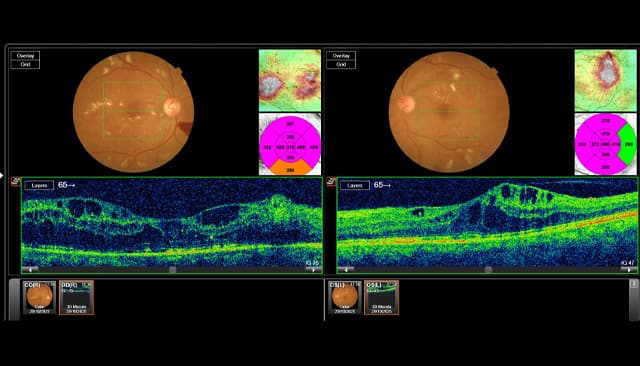

- Advanced retinal imaging (OCT)

- Fundus photography and clinical assessment by the retinal team

These investigations helped doctors carefully assess the extent of retinal damage and determine the most appropriate treatment plan.

Diagnostic Imaging & Early Diagnosis:

The evaluation confirmed Diabetic Retinopathy, a condition caused by damage to the small blood vessels of the retina due to prolonged uncontrolled diabetes.